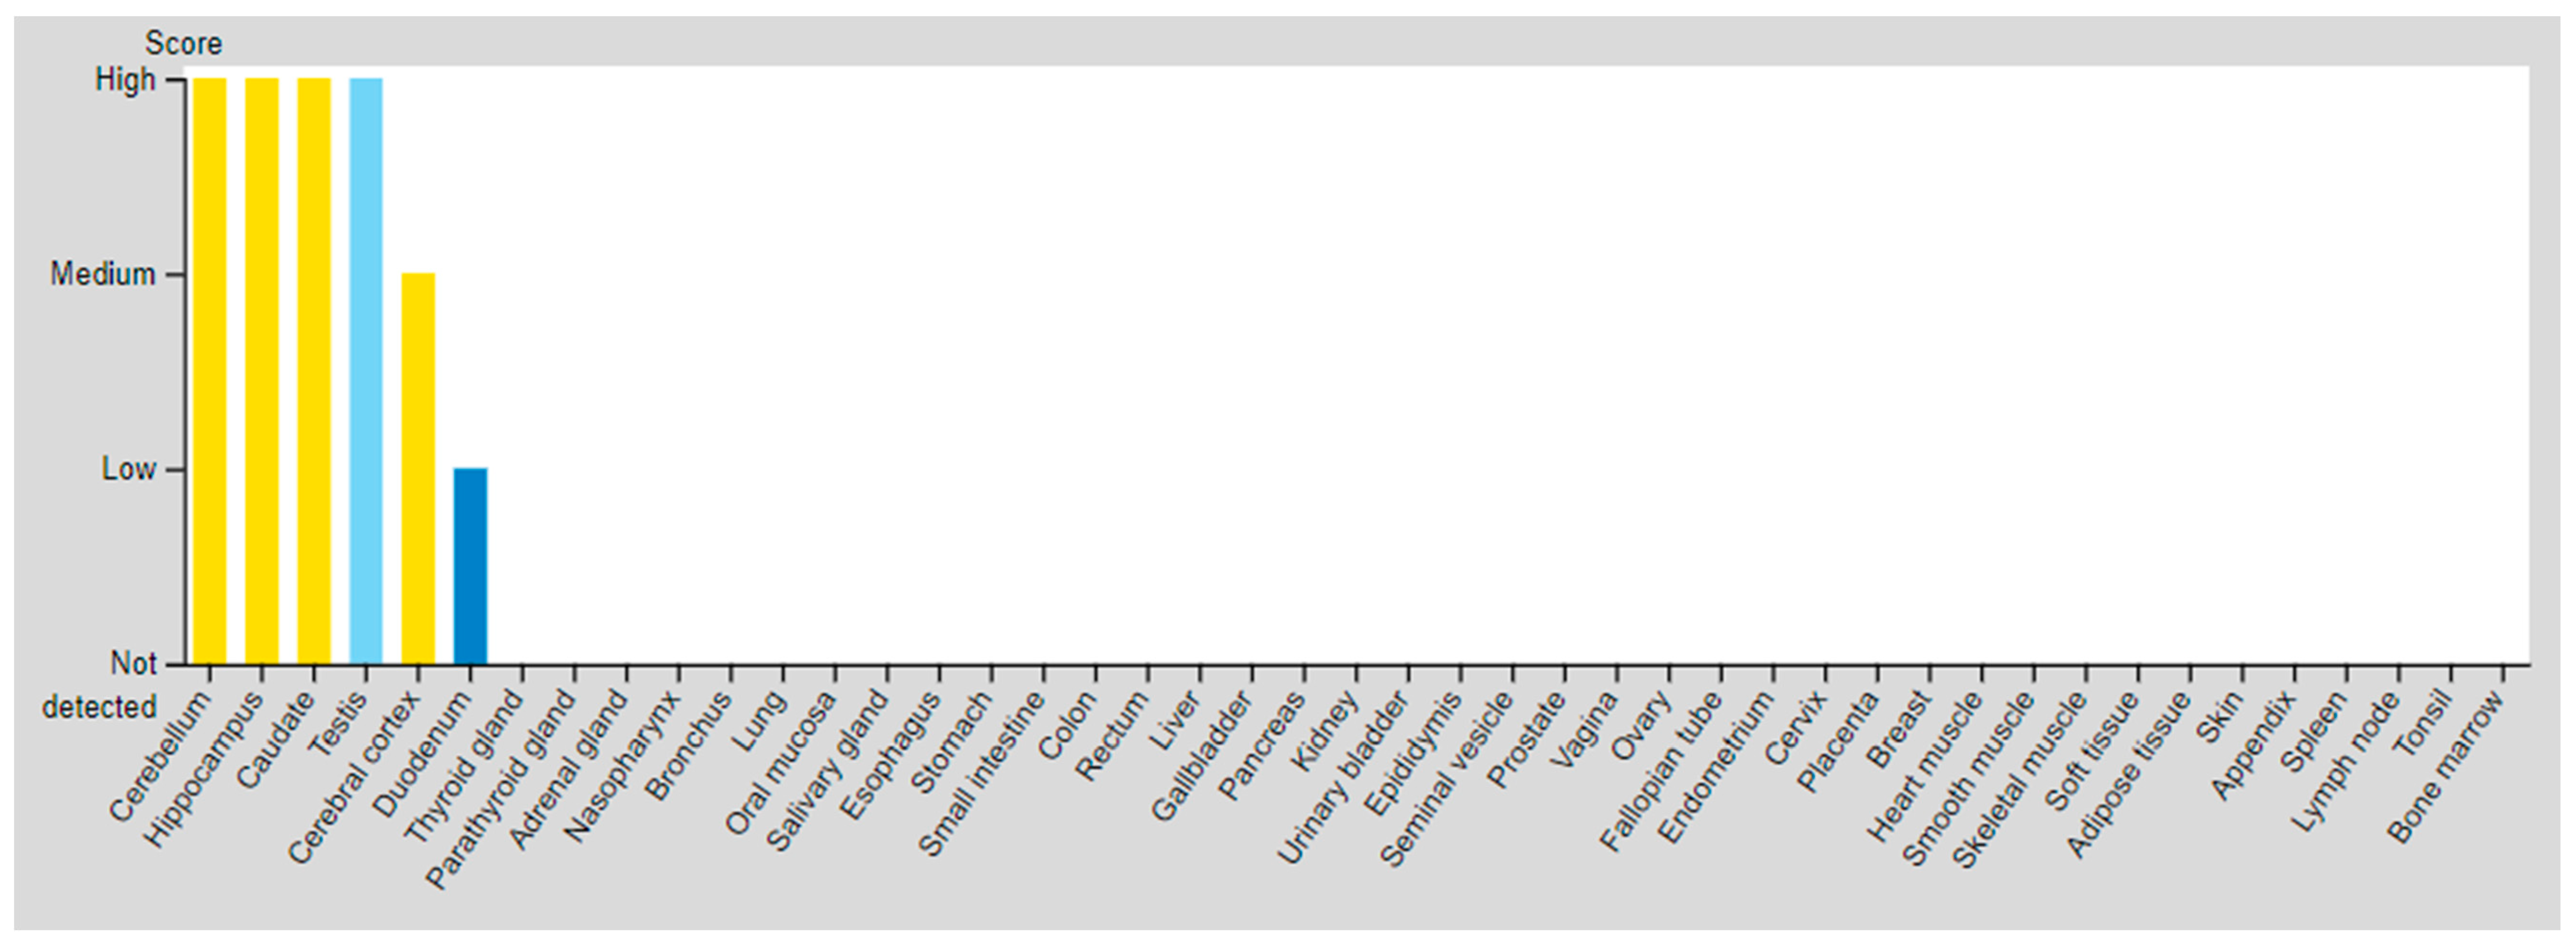

| SSTR | Critical Organs’ Tissue (High Expressed) | Critical Organs’ Tissue (Medium Expressed) | Critical Organs’ Tissue (Low Expressed) | |

|---|---|---|---|---|

| SSTR3 | Testis (Pachytene spermatocytes/Round or early spermatids) | Cerebral cortex Hippocampal formation Basal ganglia Cerebellum Testis (Peritubular cells) | Duodenum Testis (Spermatogonia cells) | |